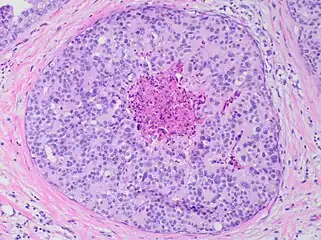

Histopathology of dystrophic microcalcifications in DCIS, H&E stain.

Ductal carcinoma in situ with comedo necrosis spanning 30% of its diameter, which is generally regarded as the minimal size to classify it as comedo.[27]